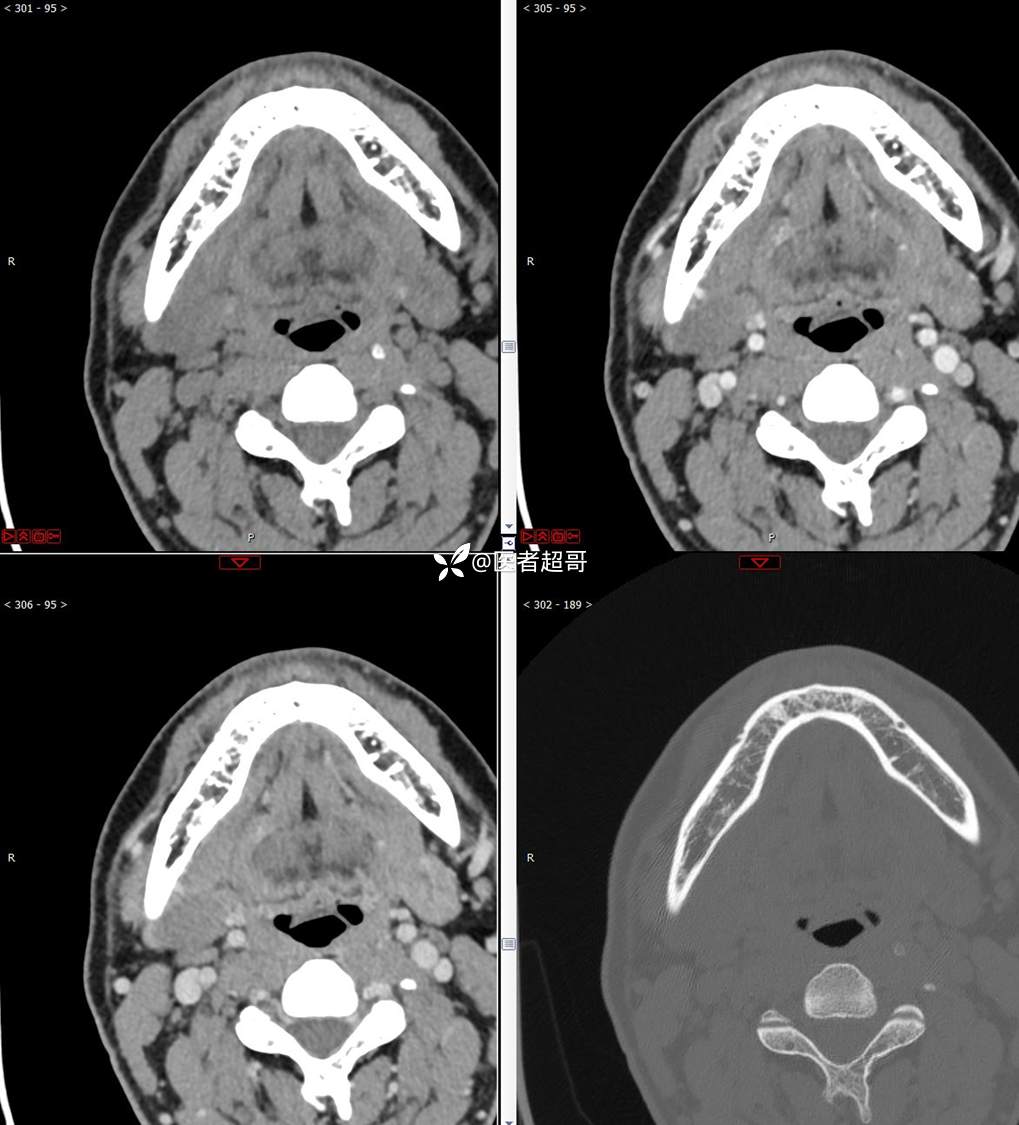

颌下腺结节:青年男性,颌下区无痛性肿物,请分析~~~

主 诉:发现右颌下区无痛性肿物1年。

现病史:患者于1年前发现右颌下区一肿物,肿物约“葡萄粒”大小,无疼痛不适,无进食时颌下区肿胀及疼痛不适。2023-10-1就诊于市中医院行超声检查;未予治疗。肿物体积无明显变化,求进一步治疗就诊于我院门诊,门诊以“颌下肿物”收入我科。患者自发病以来,神志清,精神佳,食欲好,睡眠好,大小便正常,近期体重无明显变化。